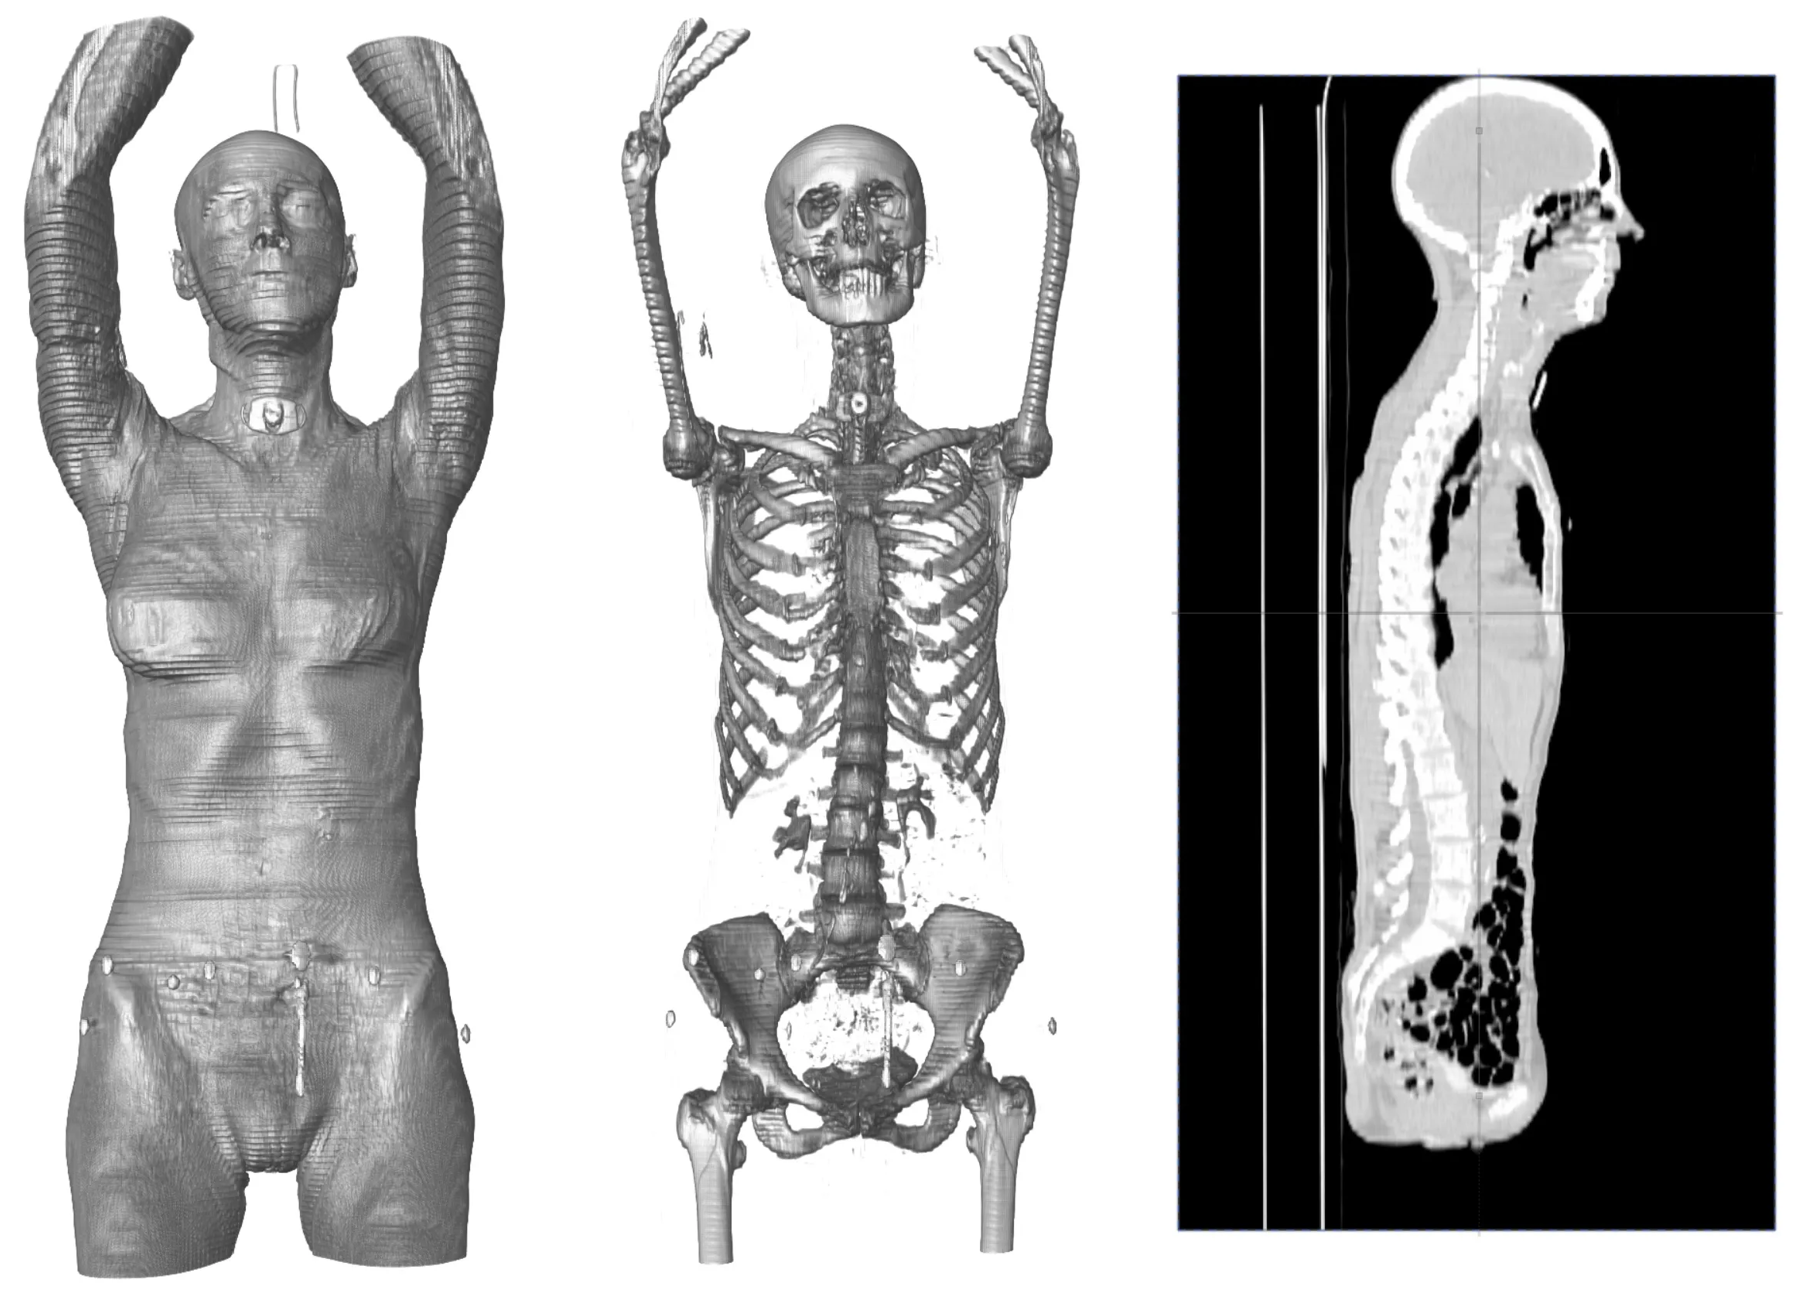

Full Body CT Scan - Female

1. 3D Visualization: Checkpoint excels in rendering 3D models from imaging data, offering interactive exploration tools that help users understand complex structures with ease. This is particularly beneficial in fields where spatial relationships and detailed structures are crucial.

3. Landmark Placement: Whether through the use of a single landmark placement point, curves, or meshes, Checkpoint supports various approaches to landmark placement to better serve the different varieties of use cases researchers and users of the tool may encounter. Very few projects, or specimens, are exactly the same....so Checkpoint needs to be robust enough to handle the subtle differences but still easy enough for users to learn and work with.